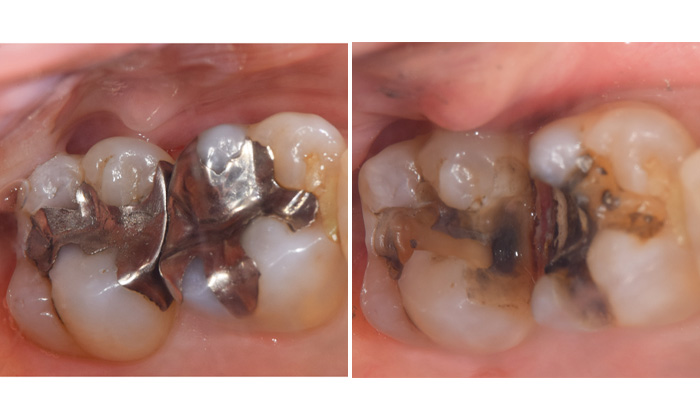

つめ物の中での虫歯

歯とつめ物の間にわずかな隙間ができてくることで虫歯になります。プラスチックですと、割れたりかけたりといったこともあります。銀歯は経年劣化しますし、銀歯をくっつける接着剤も劣化します。そのため隙間は年々大きくなる傾向にあります。

写真では10年以上前にいれた銀歯がしみるという症状があったためはずして中を確認すると、大きく虫歯になっていました。

麻布十番歯科で銀歯が虫歯になってしまった症例の口腔内写真